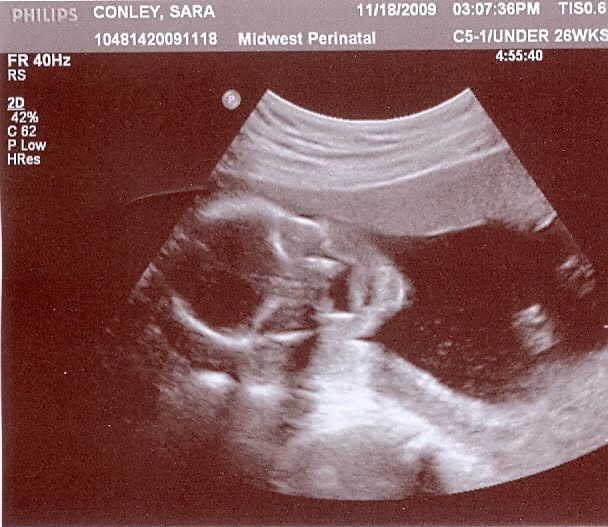

But, we're half way there at 20 weeks! We had a good report from the doctor today. They did another ultrasound today, and Darcy looked great. Brain, heart, kidneys, all that stuff looked good. She was sticking out her tongue and swallowing. So cool to watch!

Anyway, here are some updated pics - belly pictures from earlier this week and pictures from today's ultrasound. Enjoy!